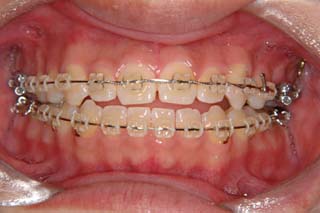

使用した主な装置名:TPB、マルチブラケット装置、オーソアンカー SMAPシステム

抜歯/非抜歯および抜歯部位:抜歯(上顎左側第一小臼歯)

マルチブラケット装置でまっすぐに並べただけの状態です。なるほど、まるで噛めてない状態なのがよく分かります。ここでよく有りがちな矯正治療だと、上の前歯と下の前歯にゴムを1日中かけて噛ませていくのですが、それでは以前と同じく、関節をずらして噛むだけの人になってしまうでしょう。特に垂直的なコントロールが必要と考えられた上顎左側に オーソアンカー SMAPシステム の植立を行いました。